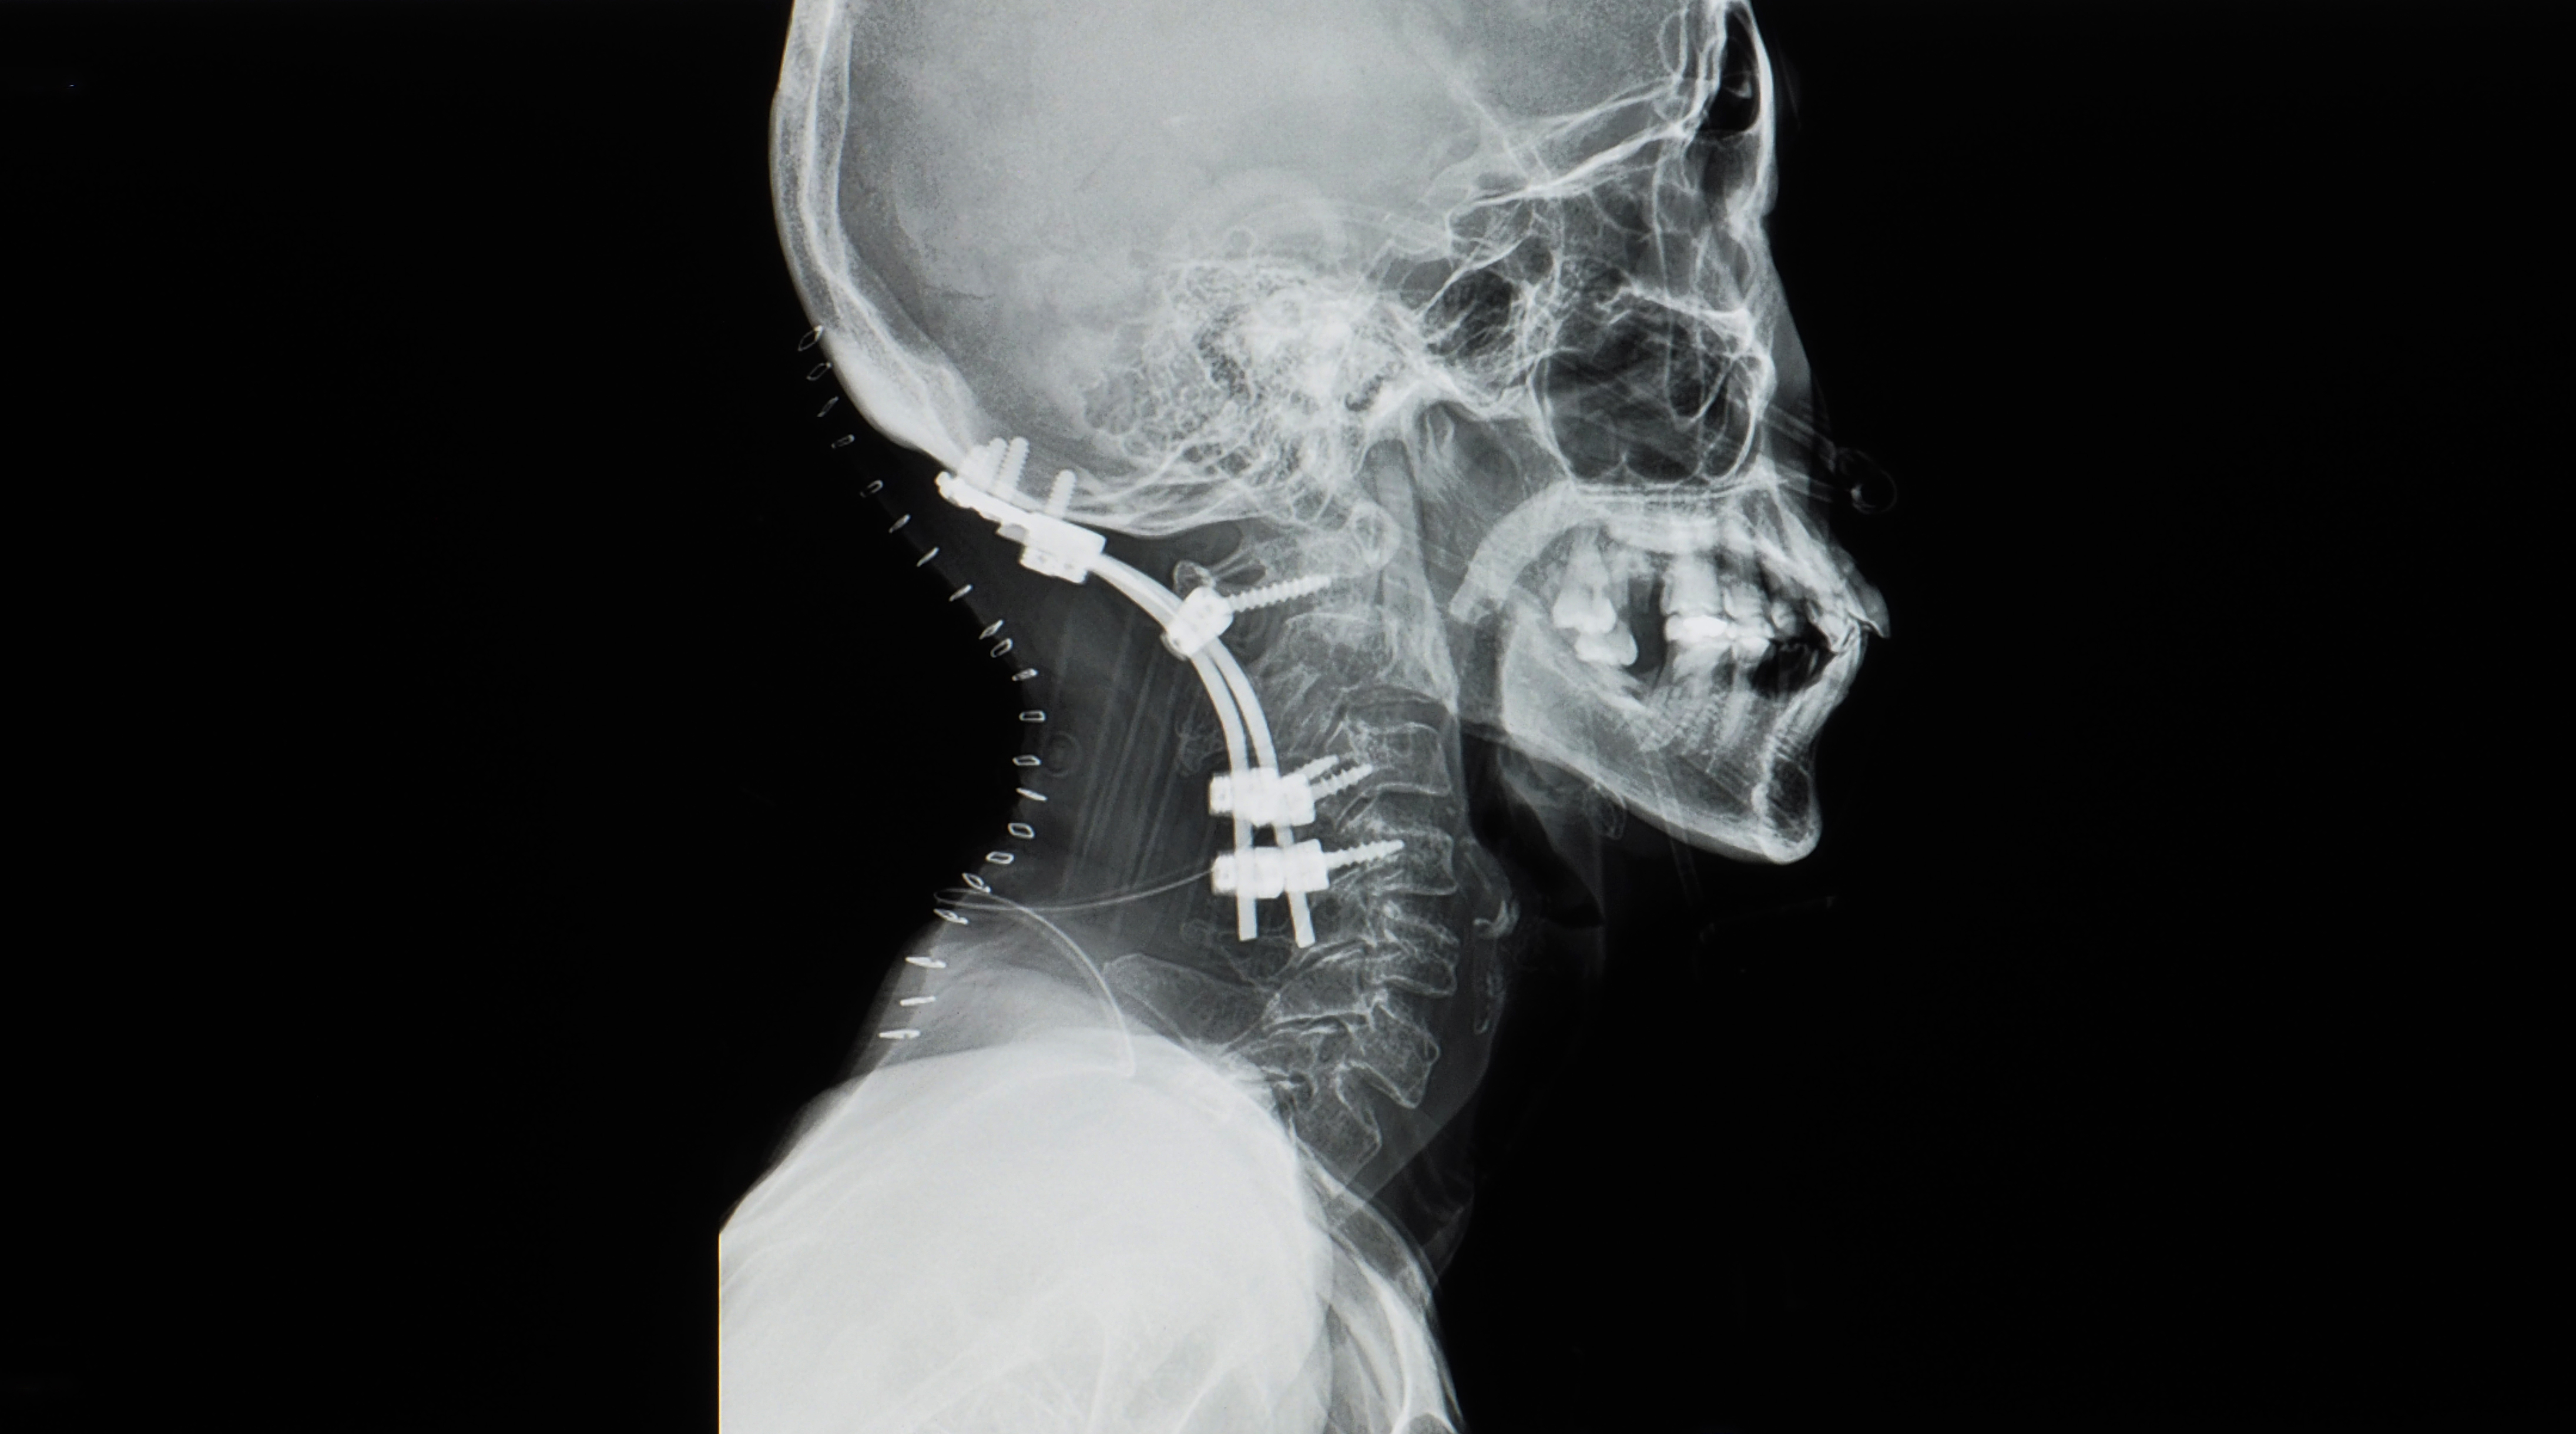

Line measurement is a subject that evaluates the misalignment of the spine and extremities through x-ray images. The line measurement evaluation method is to draw a line on the x-ray image and evaluate the alignment of the skeletal system based on the shape of the line.

More accurate diagnosis of musculoskeletal misalignment is possible through x-ray line analysis. Therefore, the treatment effect can also be expected to be maximized.

Lecture 02 - In practice, learn how to draw lines on x-ray images and evaluate them.